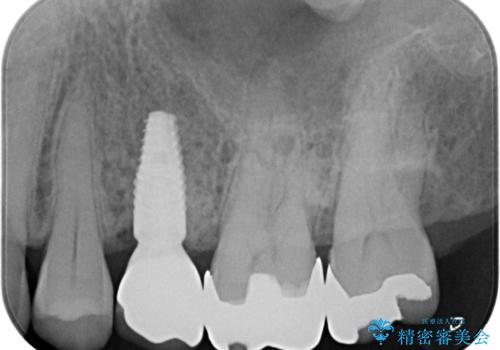

歯茎が腫れる インプラントでの治療

- 40代女性

- 10ヶ月

- 5-10回

- 左上5/インプラント:242,000円 骨増生:55,000円 カスタムアバットメント:110,000円 インプラント用仮歯:22,000円 ジルコニアクラウン:121,000円 合計550,000円費用は治療当時の料金となります